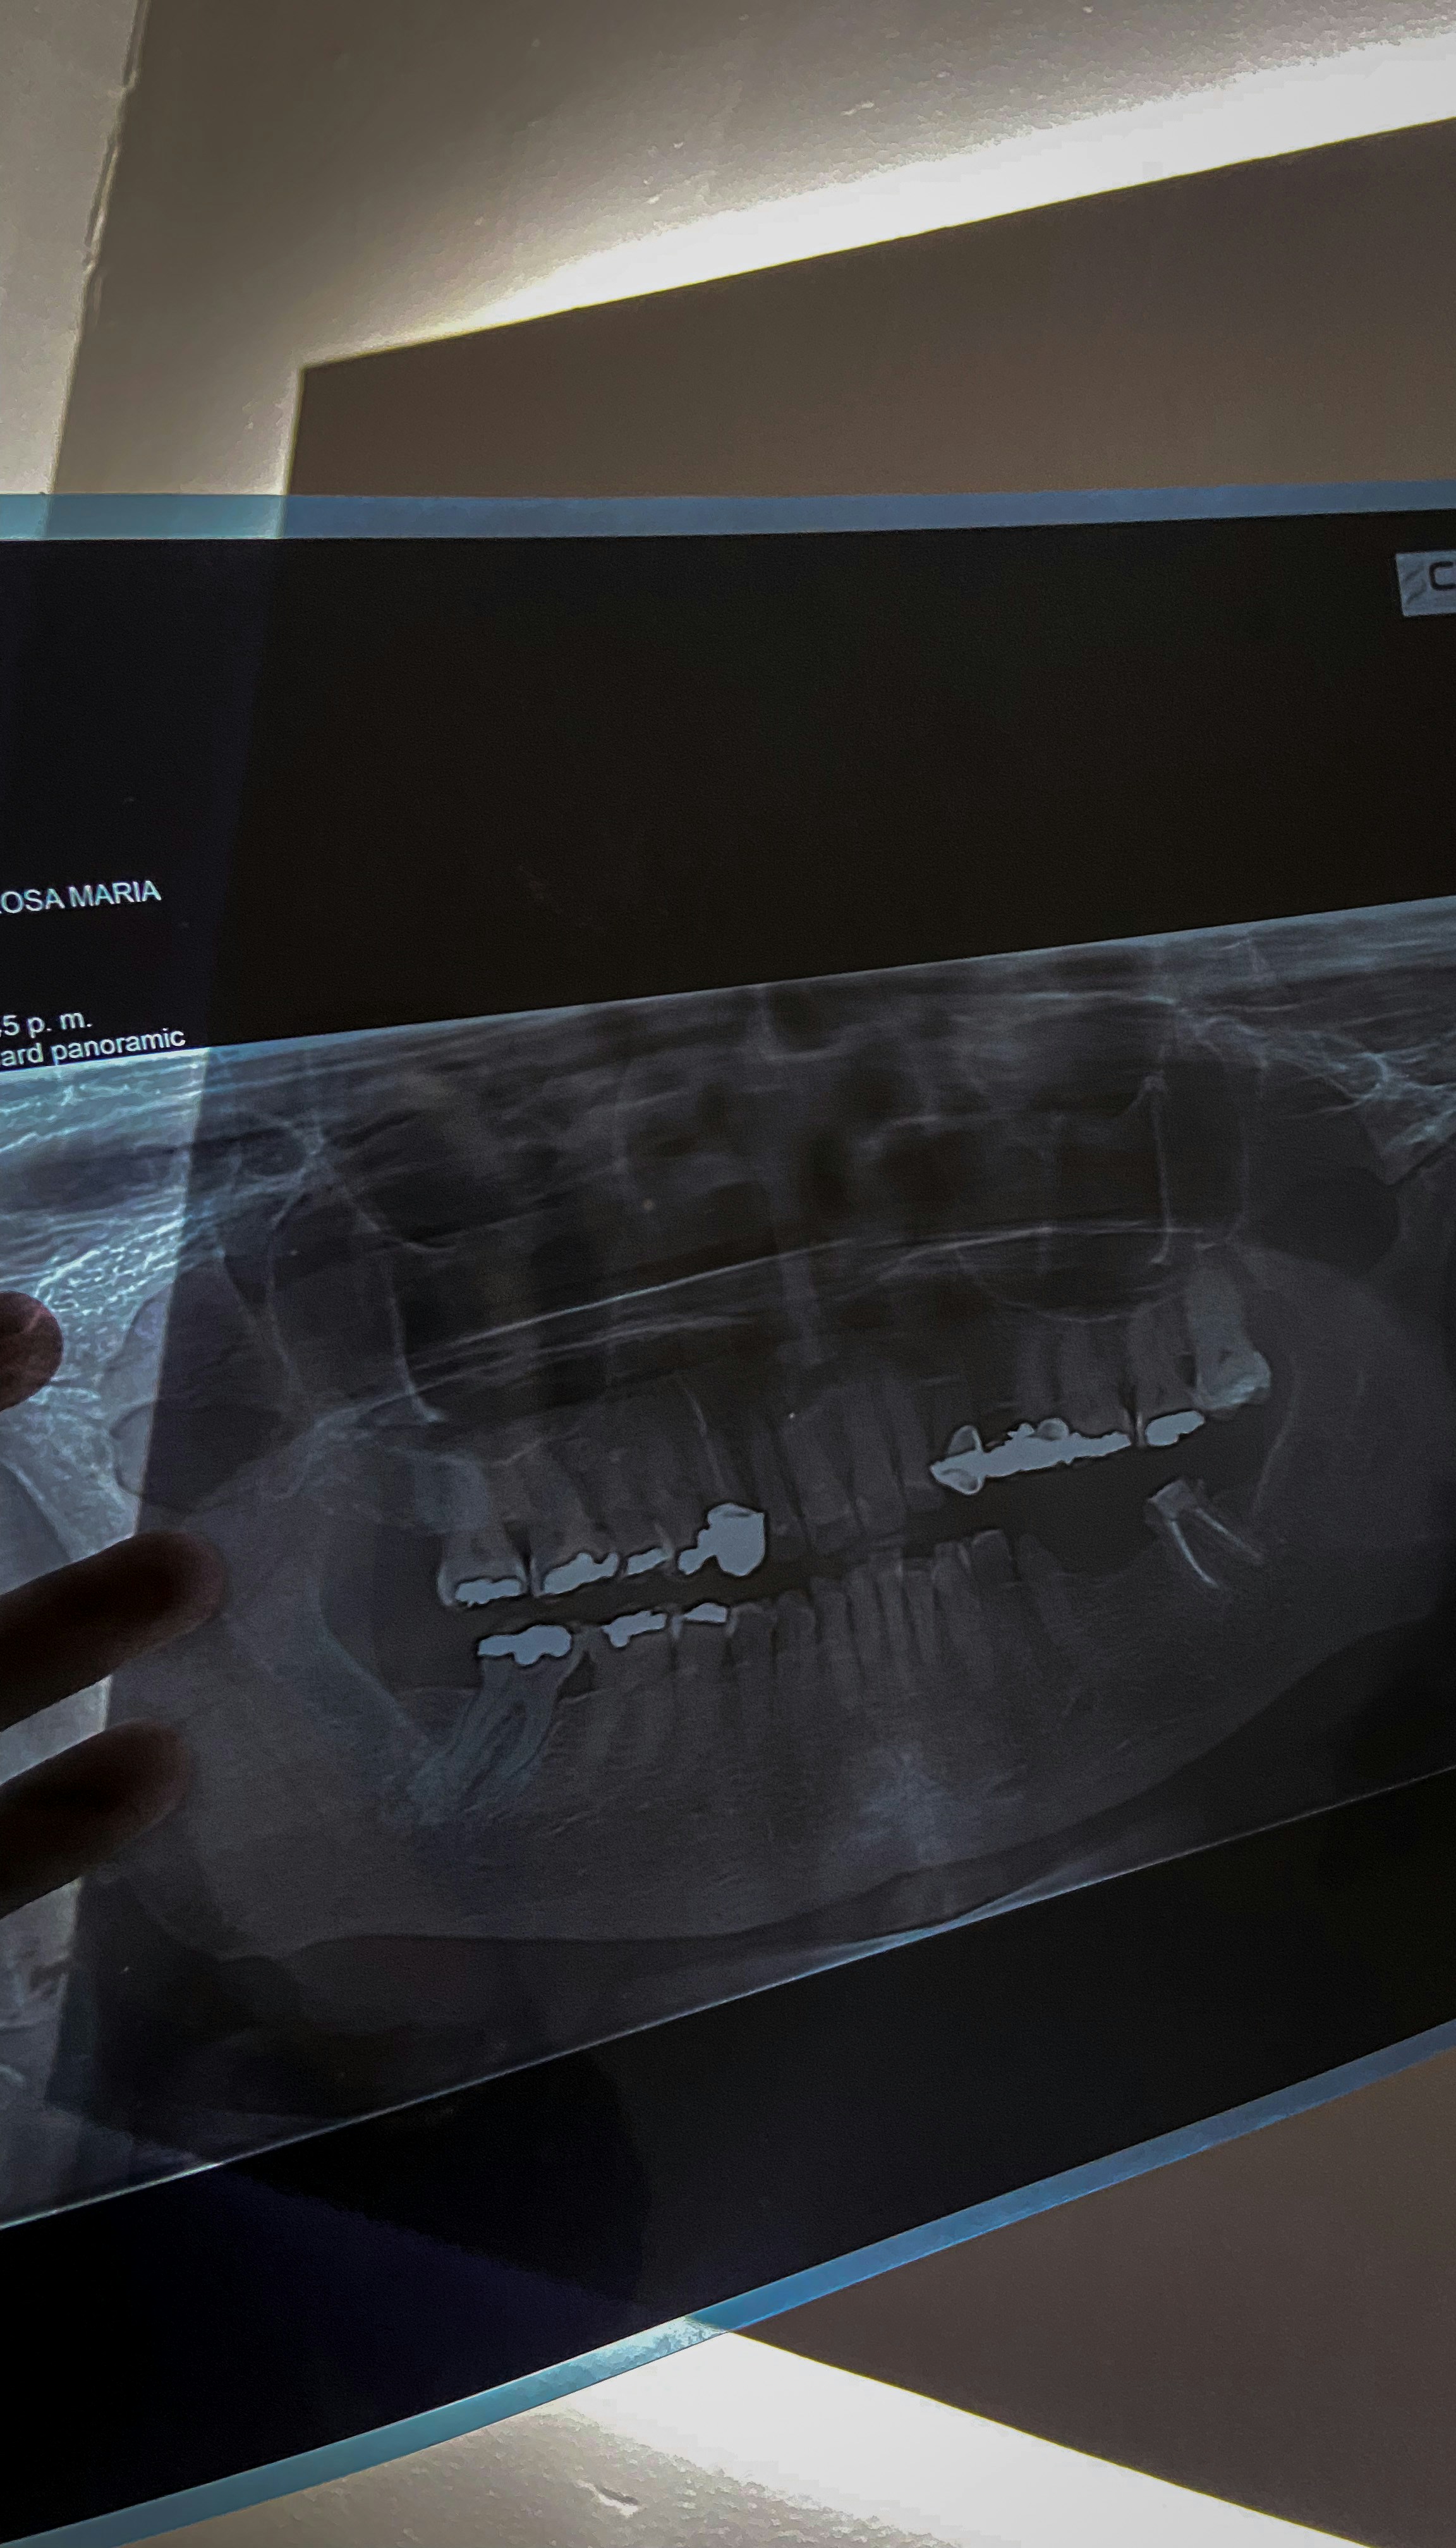

Panoramic radiography is an advanced imaging technique utilized in dentistry to capture a comprehensive view of the entire oral cavity in a single image. Unlike traditional dental radiographs, which typically focus on one or two teeth at a time, a panoramic radiographic image offers a broader perspective, encompassing both the upper and lower jaw, as well as surrounding structures. This capability makes it an invaluable tool for dental professionals in diagnosing a wide range of dental issues.

The production of a panoramic radiographic image involves a specialized machine that rotates around the patient’s head. During the process, the X-ray source moves in a semi-circular motion, capturing multiple images that are then synthesized into one continuous panorama of the dental structures. This technique significantly reduces overlap and distortion, ultimately providing a more accurate representation of a patient’s oral health.

One of the primary advantages of panoramic radiography is its ability to highlight areas that might be missed with conventional imaging methods. It allows dentists to visualize the position of impacted teeth, assess the relationship between teeth and jawbone, and identify cysts, tumors, or other abnormalities. Additionally, panoramic imaging aids in treatment planning for orthodontic work, extractions, and implant placement, making it essential in certain complex dental procedures.

Furthermore, the panoramic radiographic image is less invasive and typically more comfortable for patients compared to traditional film-based X-rays, which often require multiple exposures. By using a single panoramic image, fewer X-rays are needed overall, reducing the radiation dose to patients without compromising diagnostic capability. In the context of modern dentistry, panoramic radiography stands as a cornerstone for effective diagnosis and treatment planning, facilitating improved patient outcomes.